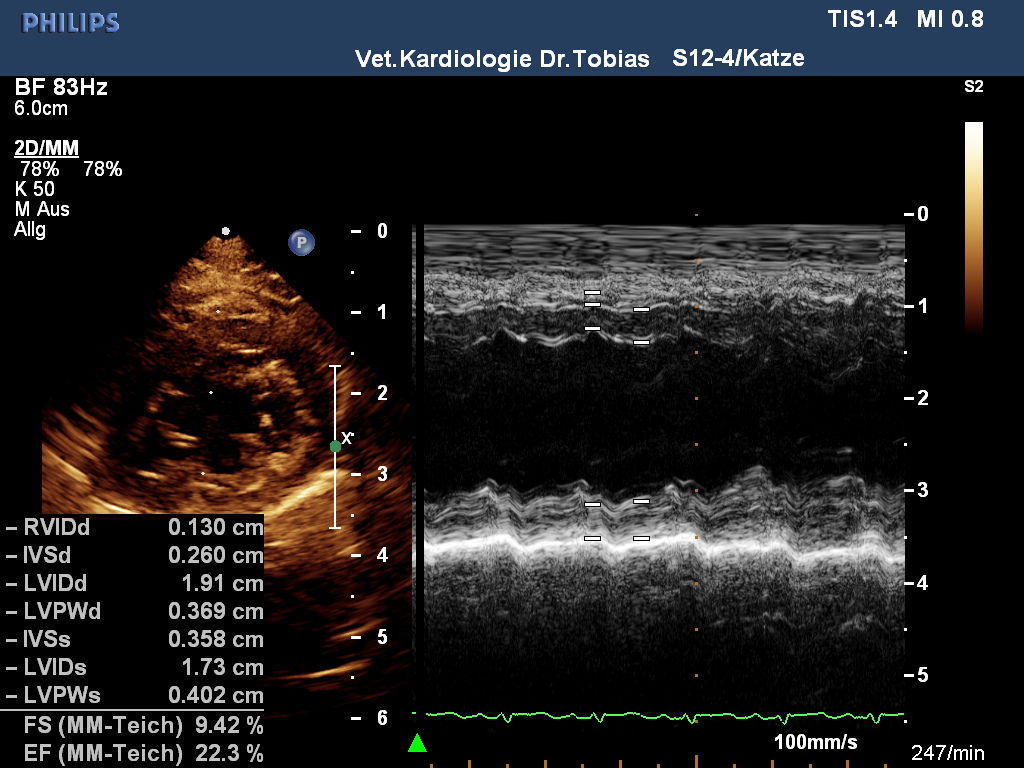

HCM- und Nieren-Schall September 2011

|

HCM normal

other diagnosis: Outburn Kardiomyopathie

aufgrund Niereninsuffizienz

sowie ggr. Mitralklappeninsuffizienz

age: 7y 9m

weight: 4.4 kg

IVSd: 3.1 mm

LVFWd: 3.3 mm

SAM: no

papillary muscles: normal

Dr.Tobias, Hannover